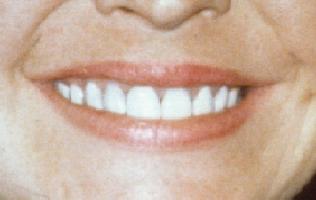

BONDING

To Cover Tetracycline Stain

This patient had been prescribed an

antibiotic called tetracycline when she was a child. Unfortunately, it

was unknown at that time that the drug would be incorporated into the

teeth and cause a dark gray coloring. A technique called bonding was

used in her case. In bonding, the white composite material that is used

for filling cavities in front teeth was layered onto the front of her

teeth. As you can see the results look great initially, however, the

technique is not very permanent, and must be redone periodically. This

technique has now been replaced by porcelain laminates. |